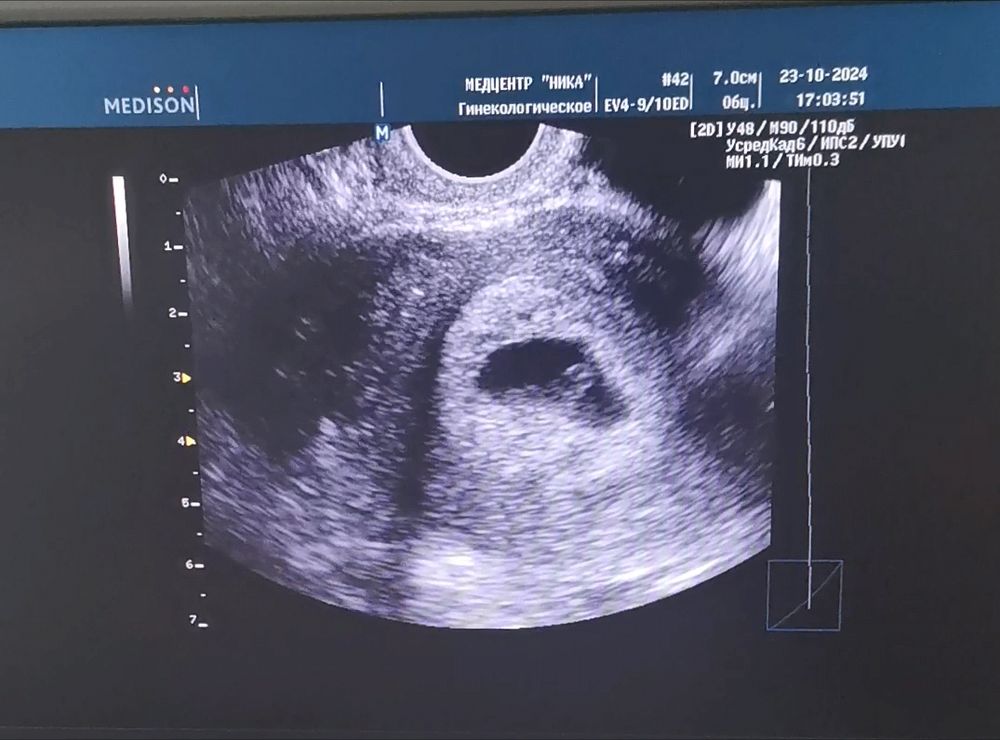

28дпп и первое узи 💍🥹

Сегодня была на первом узи. Слава Богу 🙏беременность маточная, врач и плодное яйцо, и жёлточный мешочек и эмбрион с ♥️ увидела, но послушать не дала🤷🏻♀️ Эмбрион 3,1 мм =6 нед 0 дн (по месячным 6 и 1). Поставила гипертонус, рекомендовала постельный режим, или хотя бы побольше лежать. Всю прошлую неделю немного мазало бежевым и тянул живот, сейчас, тьфу-тьфу, все ОК. На работе до 12 нед., а лучше до НГ не планирую рассказывать про Б 🫢. Поэтому про "лежать" - не вариант. На 01.11 записалась в ЖК. Как дела у Вас? Как организовываете свой постельный режим и "лечите" гипертонус? Завтра отправлю результаты узи ре, послушаю ее заключение.